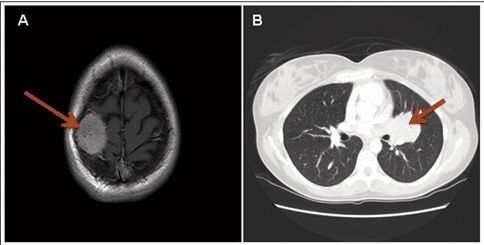

肺泡樣軟組織肉瘤CT影響檢查,圖源:sarcomahelp.org